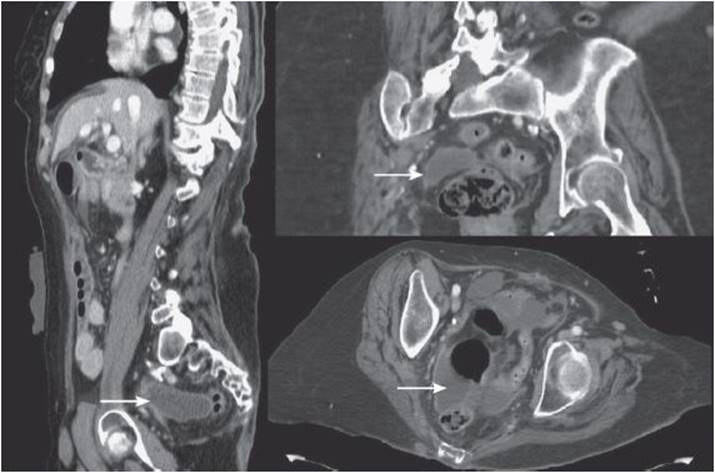

IAAs are defined on CT as a fluid collection with or without associated pockets of gas. An abscess is in contradistinction to a phlegmon, which is an inflammatory mass without identifiable fluid. Enteral contrast (either oral or rectal) can be a helpful adjunct that distinguishes loops of bowel from the abscess cavity and may provocatively assess anastomoses for leaks or fistulae. Intravenous contrast provides a pathognomonic “rim enhancement” that is seen along the outer rind of the abscess cavity. Abscess architecture can be classified as simple or loculated, referring to the degree of internal pockets or presence of septae. The location of the abscess, both absolute and relative to other organs, can be assessed and may diagnose the pathology responsible for the abscess (see Figure 22-2).

Figure 22-2. Axial, coronal, and sagittal CT reconstructions of a postoperative pelvic abscess.